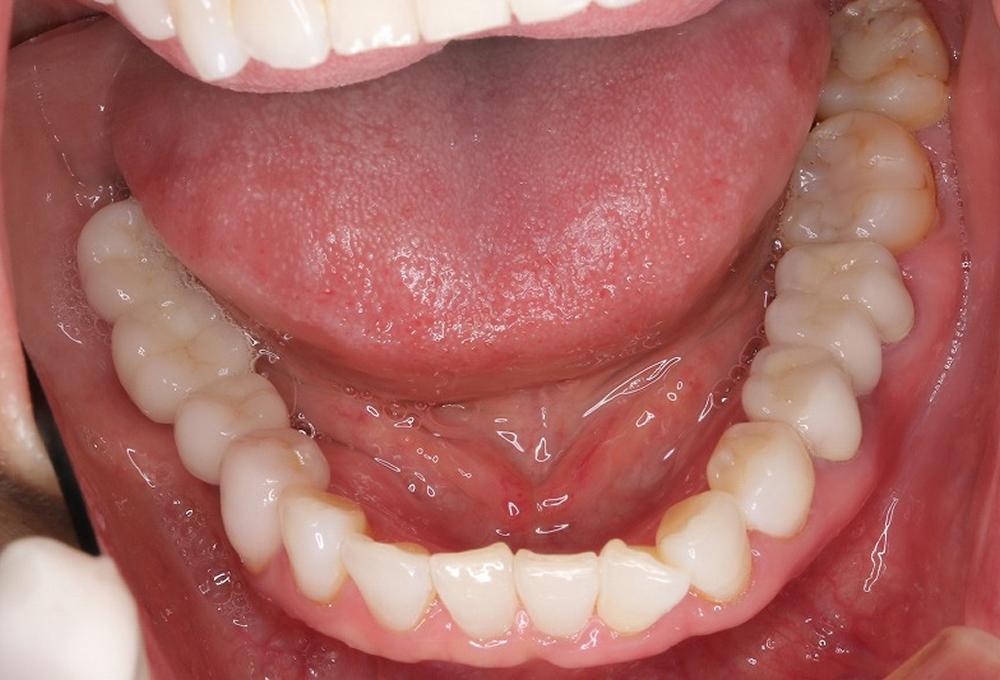

⑧術後 下顎